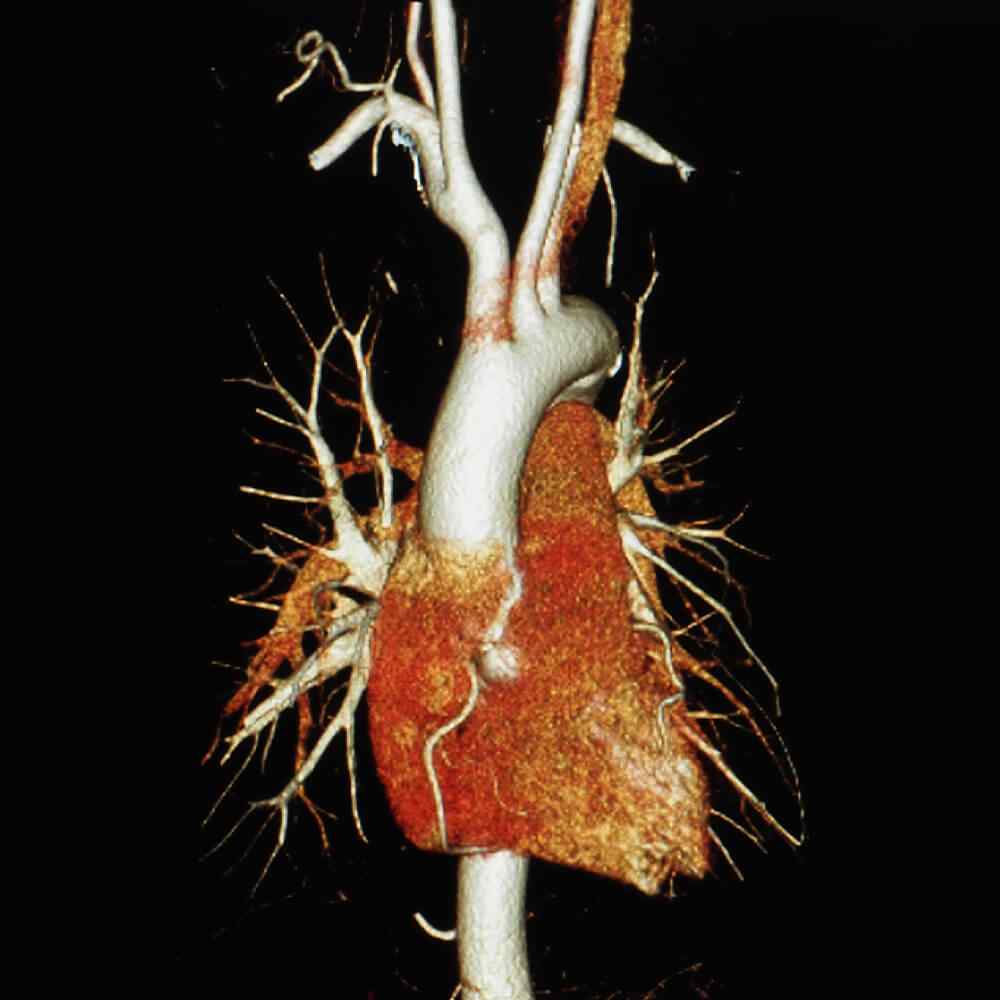

Atherosclerosis is thickening or hardening of the arteries caused by a buildup of plaque in the inner lining of an artery. Can cause a heart attack, stroke, aneurysm, or blood clot.

Atherosclerosis is the buildup of fats, cholesterol and other substances in and on your artery walls. This buildup is called plaque. The plaque can cause your arteries to narrow, blocking blood flow. The plaque can also burst, leading to a blood clot.